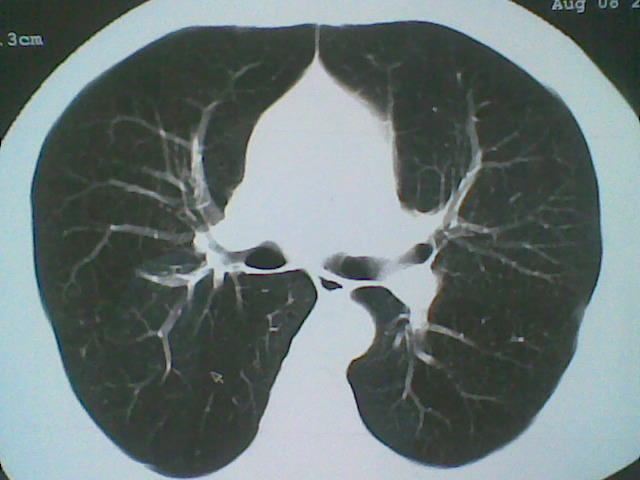

标题: CT21512:支扩伴感染?

患者女。咳嗽数天,咯血半天。

我们报的是支扩伴感染?